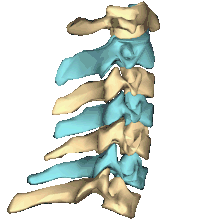

Shape of cervical vertebrae (shown in blue and yellow). Animation.

Cervical vertebrae, lateral view (shown in blue and yellow)